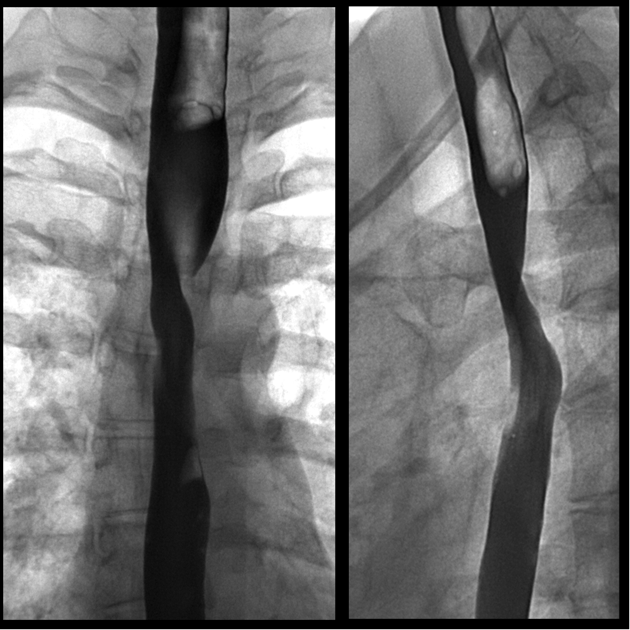

DDx for Smooth Oesophageal Strictures

DDx includes:

Inflammatory:

Neoplastic:

Others: